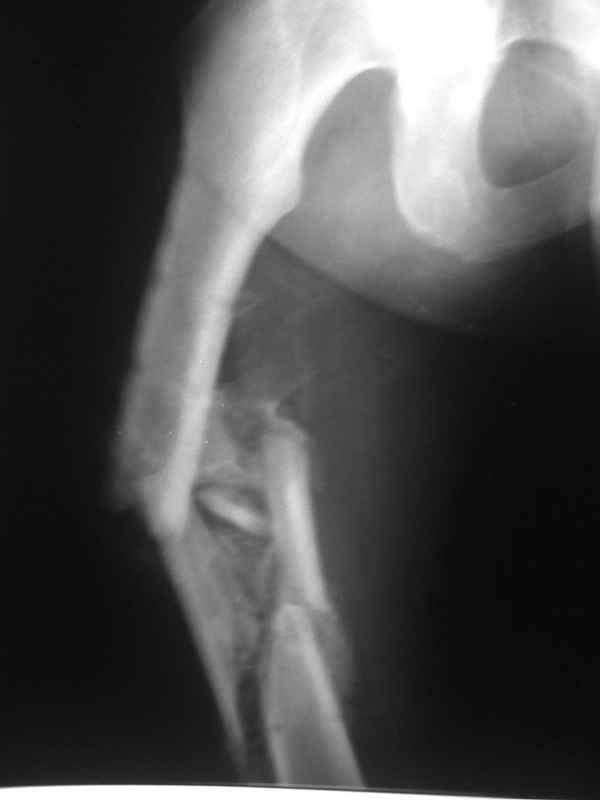

[Ortho] Неправильно срастающийся оскольчатый перелом бедра

Имя     : 005.jpg

Тип     : image/jpeg

Размер  : 16414 байтов

Url     : http://weborto.net:8080/pipermail/ortho/attachments/20110406/c06e2959/attachment-0004.jpg